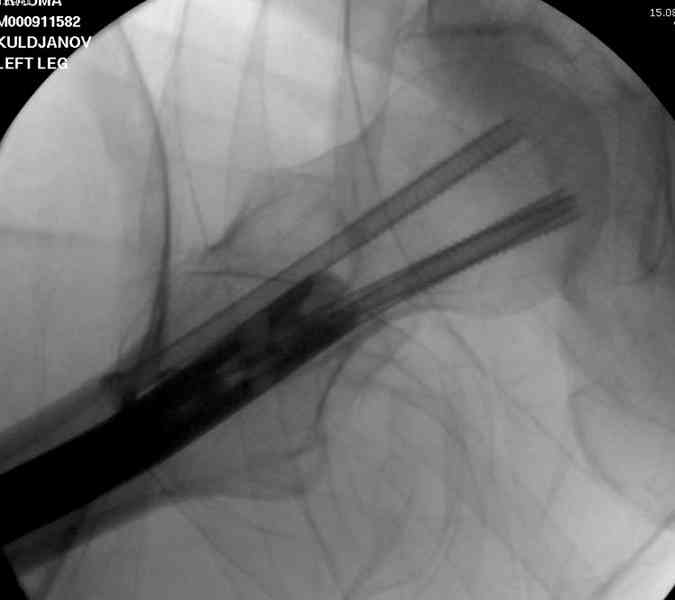

Здесь представлены снимки больного 65 лет, поступившего с диагнозом перелом

бедра после автоаварии.

В первый же день произведено антеградное штифтованием DePuy Trochanteric Nail.

На второй день (7) обнаружен пропущенный перелом,

сделаны Компьютерная Томограмма

и проведены шурурпы через и спереди штифта без удаления.

Послеоперационные снимки